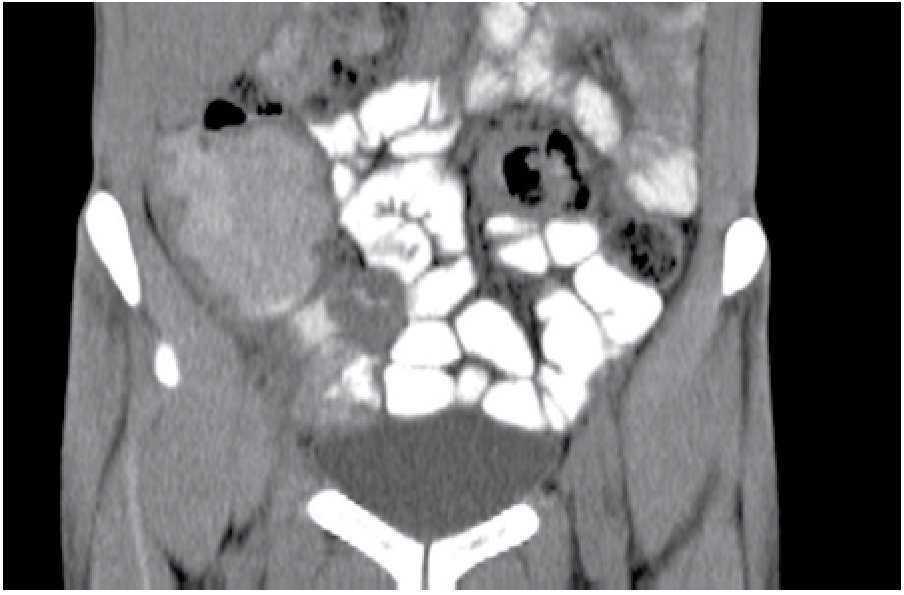

Paciente masculino de 28 años de edad, originario y residente de Chiapas, con un año de evolución, quien presentaba cuadros de estreñimiento y dolor abdominal ocasional, pérdida de peso de 7 Kg en seis meses, además de consumo de leche sin pasteurizar en dos ocasiones. Fue valorado por múltiples gastroenterólogos, se le realizaron estudios de endoscopia y colonoscopia, sin llegar a un diagnóstico preciso. Por nuevo cuadro de cuatro días de evacuaciones disminuidas en consistencia, 7/día, sin moco, ni sangre, con tenesmo y pujo tras la ingesta de cualquier alimento, dolor abdominal 9/10, asociado a náusea, sin vómito, con escalofríos y elevación térmica, acudió a Urgencias para valoración. En los estudios se evidenció hemoglobina de 12.3 g/dL, plaquetas 155 000 mm3 y VSG 35 mm/h. En TC se observó hepatoesplenomegalia, adenopatías y zonas de estenosis en íleon terminal (Figuras 1 y 2). Se realizó enteroscopia retrógrada de un solo balón, en donde se observaron úlceras lineales en íleon medio y terminal con engrosamiento de la mucosa y la válvula ileocecal con colon normal (Figura 3). La evaluación de patología mostró ileítis aguda ulcerada y crónica granulomatosa, asociada con micobacterias (Figuras 4, 5 y 6). El paciente se egresó del hospital para manejo ambulatorio con medicamentos antifímicos.

Figura 1.Válvula ileocecal con zona de engrosamiento de mucosa y zonas de estenosis.

Figura 2. Adenopatías pericecales.